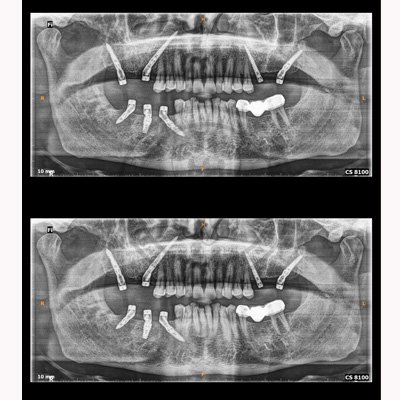

Case – 11 Baleram